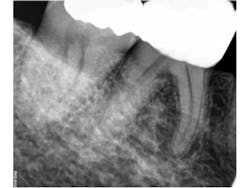

Clinically, tooth No. 29 had a PFM crown, No. 30 had been restored with a full gold crown, and No. 31 had a mesio-occlusal amalgam restoration. Sensibility testing in this quadrant revealed that tooth No. 30 had a slightly “different” sensation to touch, but all other tests were WNL, including cold testing. Radiographs revealed that the mesial root of tooth No. 30 had a roun, mixed radiopaque/radiolucent lesion. Additionally, this lesion did not appear to be centered on the apex of this root (Fig. 1). Due to the mixed appearance and position around the root, a cone beam CT was obtained to further evaluate this area.Fig. 1: Periapical radiograph showing a round, mixed radiolucent/radiopaque lesion associated with the mesial root of tooth No. 30. Note that the lesion is not centered around the apex of the tooth.